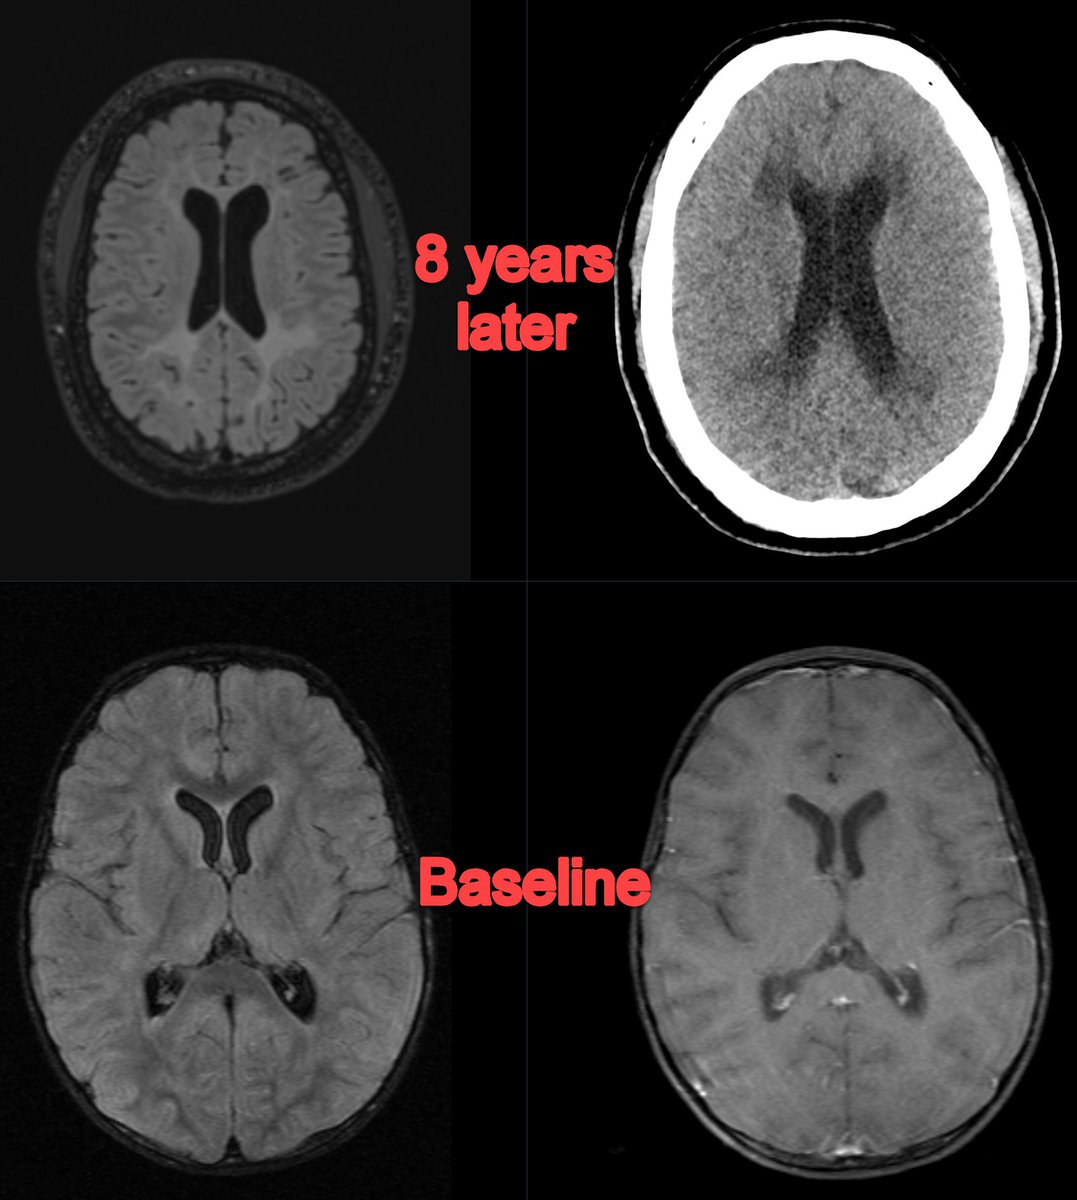

🧠ARIA in Focus: Imaging Criteria, Reporting Recommendations, and Case-Based Insights